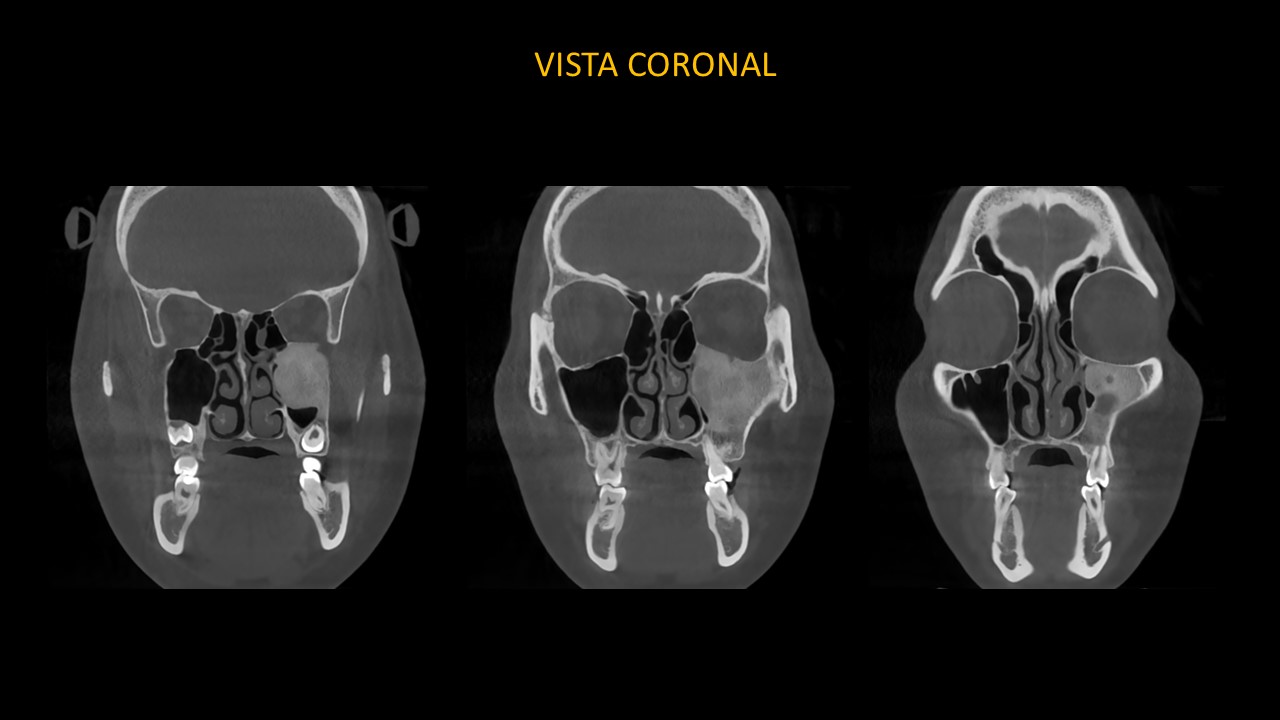

Figura 3

En las vistas coronales (Figura 3), se evidencia el borramiento y expansión leve de la cortical basal de cavidad orbitaria, así como el borramiento de la cortical del conducto infraorbitario, compromiso de la pared medial de seno maxilar izquierdo y pared lateral de fosa nasal izquierda